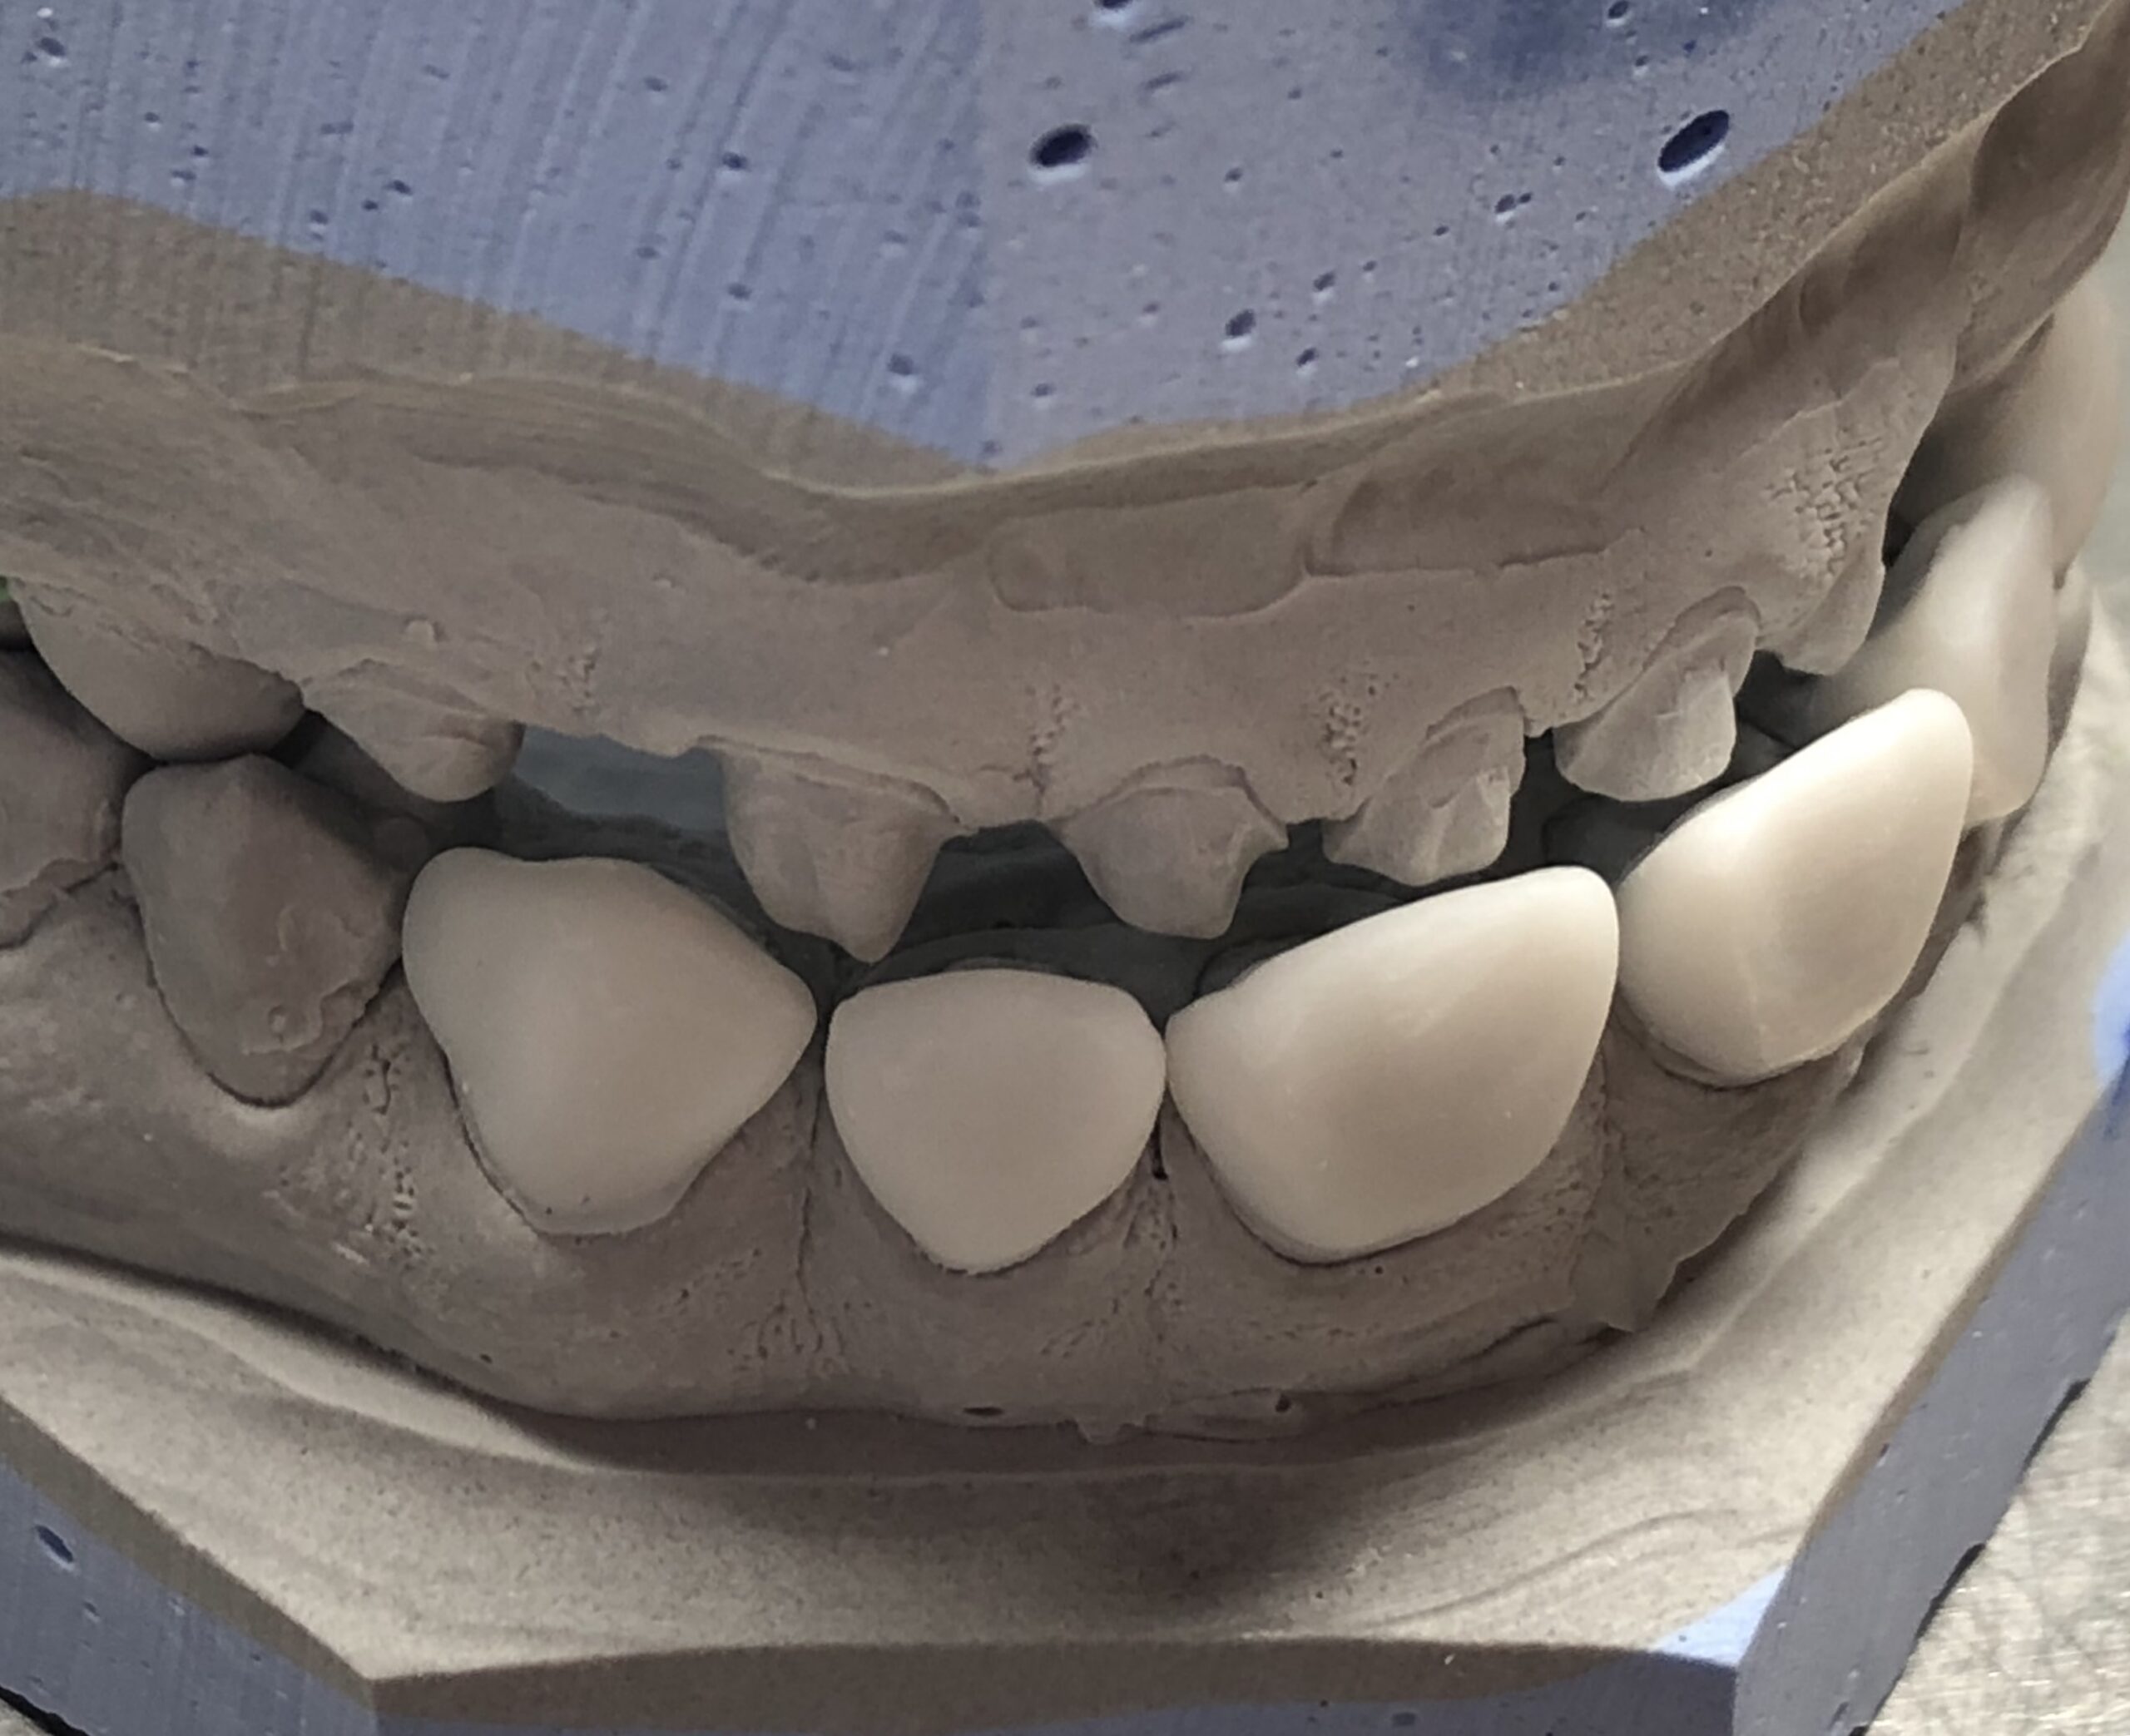

Nos réalisations : Conjointe

Céramique sur Zircone

La zircone présente une très grande résistance à la flexion (plus de 1 400 Mpa).

Translucide, elle reflète la lumière aussi naturellement que l’émail.

Biocompatible elle est garante d’une excellente intégration gingivale.